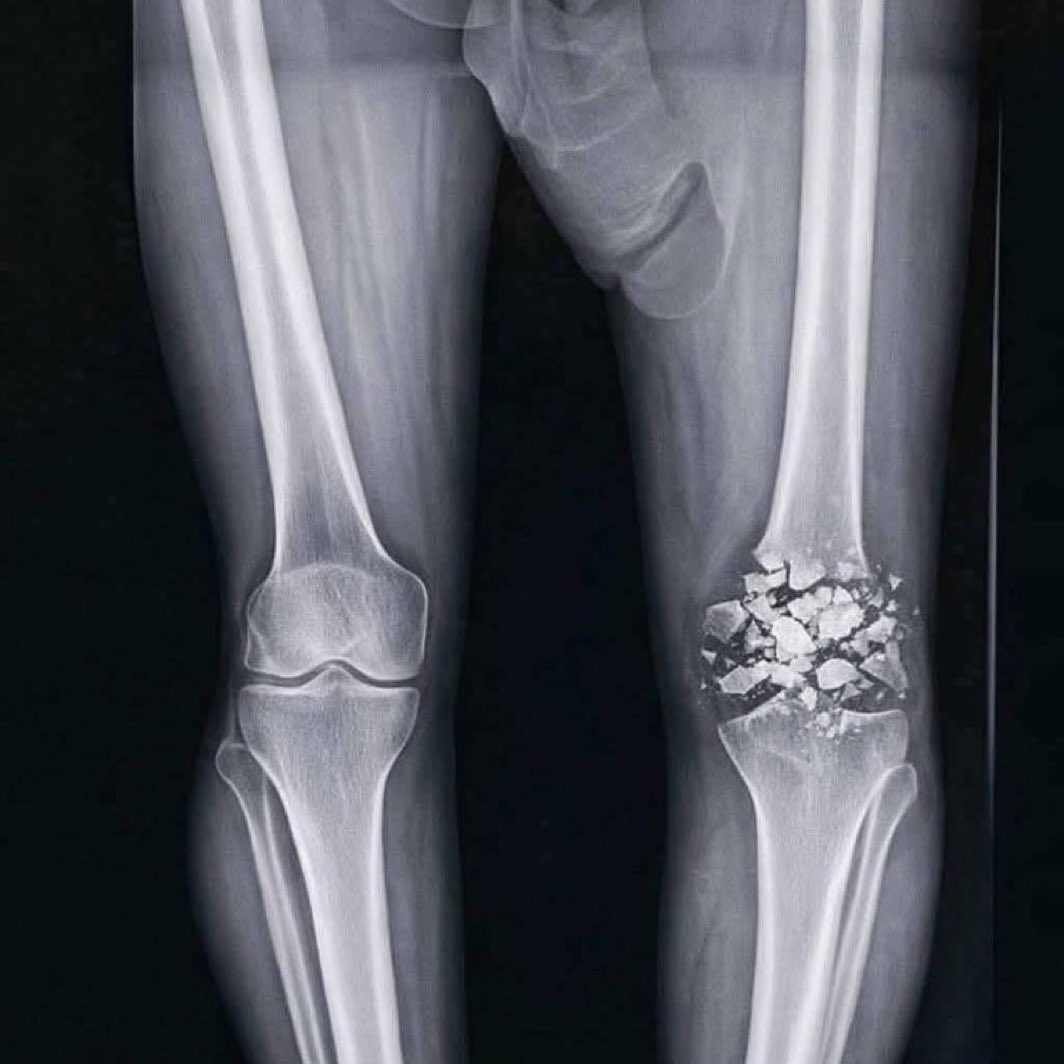

Adin Ross shared X-ray photos of his injured knee, giving fans a closer look at the damage and sparking concern across social media hoping for a speedy recovery...💔🙏

NSNB tweet mediaNSNB tweet media